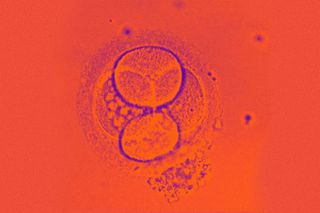

In a groundbreaking development, a team of scientists from the U.K. and the U.S. have created synthetic human embryos by reprogramming stem cells — circumventing the need for sperms and eggs, in the process. These are model embryos, they note, that are at the very initial stages of human development, and can help advance the study of genetic disorders and improve understanding of the causes of miscarriages. While they, reportedly, lack most internal organs, they do include cells that would eventually form the placenta, yolk sac and the final embryo.

“[T]hey are very exciting because they are very looking similar to human embryos and very important path towards discovery of why so many pregnancies fail, as the majority of the pregnancies fail around the time of the development at which we build these embryo-like structures,” Magdalena Zernicka-Goetz, a Polish-British developmental biologist whose lab has been involved in the development, told CNN.